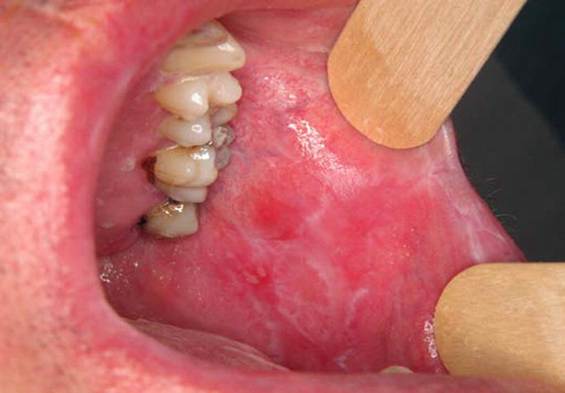

A patient presents with a persistent red lesion on the lateral border of the tongue. Biopsy confirms squamous cell carcinoma. Which of the following viral infections is most strongly associated with this malignancy?

Options:

A) Epstein–Barr virus

B) Cytomegalovirus

C) Herpes simplex virus

D) Human papillomavirus

Correct answer: D) Human papillomavirus